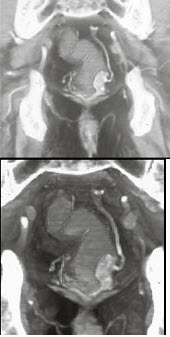

男,50岁,血便,大便形状改变,CT如图,应考虑为( )

A:直肠息肉

B:直肠内粪便

C:直肠癌

D:直肠腺瘤

E:直肠淋巴瘤